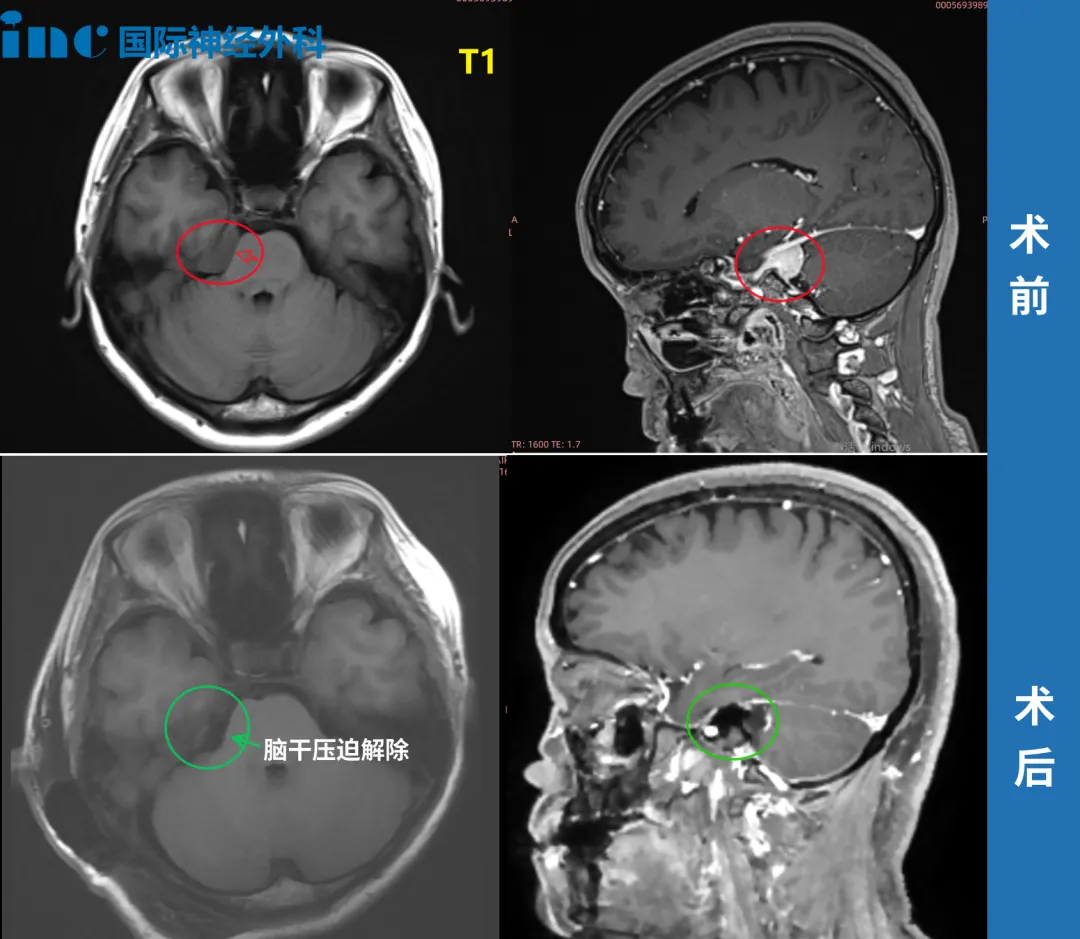

脑膜瘤伽马刀治疗无效,一台手术顺利全切

术前情况:2021年9月,50多岁的钟女士在体检中意外查出CPA区脑膜瘤。当时医生告诉她,右侧桥小脑角(CPA)区占位,肿瘤位置附着岩谷、临近面听神经,且已经压迫脑干,手术治疗伤及神经的风险很大,也就是说如果手术做不好,钟女士可能以后开口吃饭、睁眼看东西的力气都没有了,也很可能失去视力和听力。

手术情况:2022年巴教授中国行中,成功主刀手术肿瘤全切,无新发神经功能损伤。术后一天ICU查房,钟女士状态清醒,和教授交流顺畅。术后五天查房,钟女士状态良好,连声感谢巴教授并和教授开心合影。病理结果脑膜瘤WHOI级,良性预后很好,术后将不再需要反复放化疗,她可以像正常人一样生活。

▼术前术后MRI对比

术后情况:术后10天,我们对患者爱人进行了采访,给相同经历的患者家庭带来一些合适的参考信息。

钟女士早已恢复了正常生活,术后进行定期的影像随访。术后九个月时,钟女士收到了巴教授回复的随访邮件,没有复发、无残留。